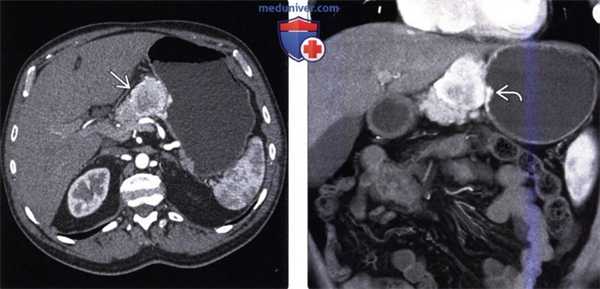

Частота нейроэндокринной опухоли (НЭО) желудка увеличилась до 41% всех НЭО ЖКТ в основном за счет распространения эндоскопических методик. У большинства пациентов с НЭО желудка опухоли специфически не проявляются и обычно становятся случайной диагностической находкой. В отличие от НЭО тонкой кишки, у пациентов с НЭО желудка типичный карциноидный синдром встречают очень редко. Поскольку эти опухоли способны на ранних стадиях метастазировать в печень и лимфатические узлы даже при небольших размерах, необходима адекватная оценка стадии опухоли. При наличии гипергастринемии хорошо дифференцированная НЭО может быть отнесена к типу I, при котором отмечают гипергастринемию, хронический атрофический гастрит и энтерохромаффино-подобную клеточную гиперплазию; к типу II, при котором гипергастринемия связана с множественной эндокринной неоплазией типа I (МЭН-1) и синдромом Золлингера-Эллисона; к типу III, не ассоциированному с гипергастринемией (спорадический тип).

• Тип I НЭО желудка — самый распространенный (75-80% НЭО желудка), чаще встречаемый у женщин (в 2-3 раза чаще, чем у мужчин). Обычно представлен множественными и мелкими (менее 1 см) полиповидными образованиями, расположенными в области тела и дна желудка. Тип I НЭО желудка обычно имеет доброкачественное течение и редко метастазирует в лимфатические узлы (2% пациентов с опухолями I типа).

• Тип II НЭО желудка ассоциирован с синдромом МЭН-1, опухоль обычно более крупная (чаще более 1 см) и имеет более агрессивное клиническое течение (местные метастазы до 30%). У пациентов с НЭО типа II в утолщенных губовидных складках и стенке желудка наблюдают множественные полипы или массы, иногда изъязвленные.

• НЭО желудка типа III представляет собой спорадическую, обычно больших размеров (чаще более 2 см) одиночную опухоль, которая может изъязвляться. Для таких опухолей характерно агрессивное клиническое течение с местной инвазией и ранними метастазами, особенно если размер опухоли превышает 3 см (Christopoulos и Papavassiliou, 2005; Johnson et al., 2010). При контрастной рентгенографии карциноидные опухоли желудка выглядят в виде небольших (менее 2 см) «сидячих» полиповидных образований. При КТ эти опухоли обычно выглядят как небольшие гиперденсивные полипы. У пациентов с ассоциированным синдромом Золлингера-Эллисона наблюдают диффузное утолщение губовидных складок и множественные полипы или массы. Дифференциальную диагностику карциноидных опухолей желудка, представляющих собой мелкие гиперденсивные полиповидные образования, проводят с мелкими стромальными опухолями ЖКТ, гломусными опухолями и гетеротопией поджелудочной железы. Нейроэндокринные карциномы ЖКТ наиболее часто встречают в желудке (до 59% всех нейроэндокринных карцином ЖКТ). При КТ нейроэндокринные карциномы желудка обычно визуализируют в виде выраженного гомогенного усиления сигнала в артериальную фазу с дальнейшим его усилением в венозную фазу при обильном кровоснабжении опухоли. При распространении опухоли в печень печеночные метастатические поражения обычно выглядят в виде гомогенного накопления контраста (Johnson et al., 2010).